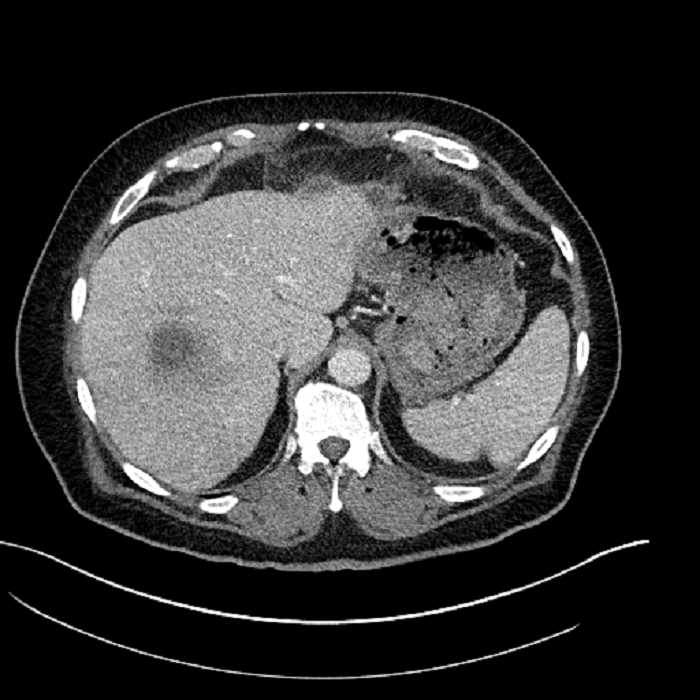

• Large fluid density structure in hepatic segments 7 and 8 measuring 10 x 7 x 7 cm with internal septation and circumferential ill-defined low density compatible with edema

• Peripherally enhancing subcapsular collections along the anterior margin of the left hepatic lobe measuring 3 x 1 cm and 2 x 1 cm

• Clearly marginated fluid density structure in segment 7 and several other scattered tiny hypodensities, which likely represent cysts

Acute sigmoid diverticulitis complicated by a small contained perforation and a large abscess in the right hepatic lobe. Additional small subcapsular abscesses along the anterior margin of the left hepatic lobe.

• The classic CT imaging appearance is a double target sign with internal low density surrounded by an internal enhancing rim (capsule) and a low density external rim (edema)

Hepatic abscess showing the double target sign with low density internally surrounded by a thin inner enhancing rim (red arrow) and ill-defined outer low density rim (yellow arrow). Blue arrow indicates an internal septation. Red arrows: additional smaller subcapsular abscesses. Red arrow: focal contained perforation associated with diverticulitis.